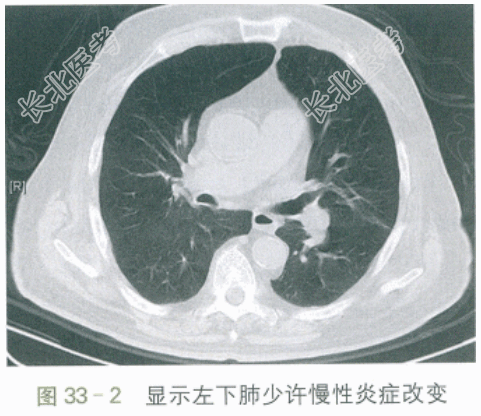

胸部平扫CT:肺气肿,两肺少量慢性为主炎症。如图33-1、图33-2所示。